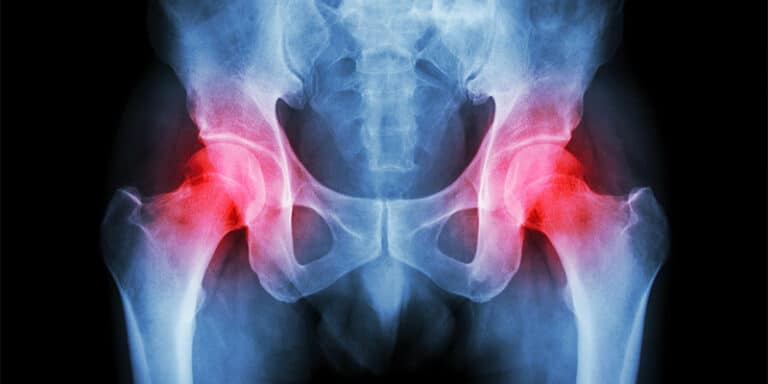

الم مفصل الحوض اسبابه وعلاجه